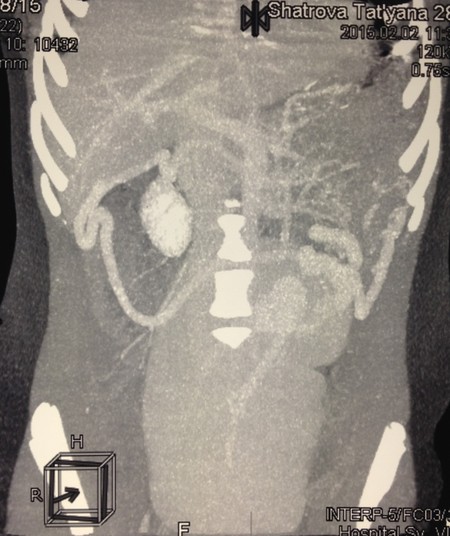

Селезеночная вена шириной до 12мм, значительно удлинена, имеет извитой ход, делает несколько изгибов, впадает в портальную вену в типичном месте (Рис. 5).

Рис. 5. Компьютерная томография. Селезеночная вена шириной до 12мм, значительно удлинена, имеет извитой, спиралевидный ход.

У больных с блуждающей селезенкой при пальпации живота может выявляться объёмное, легко смещаемое в область левого подреберья образование брюшной полости. Важное значение имеет УЗИ с определением кровотока в сосудах селезенки [1,2,6]. Спиральная компьютерная томография с контрастированием, а также МРТ позволяют визуализировать извитые сосуды ворот селезенки [5]. В обоих наших наблюдениях заподозрить перекрут блуждающей селезенки удалось при УЗИ. Наиболее характерным симптомом при спиральной компьютерной томографии, наряду с аномальным положением органа, был контрастируемый спиралевидный ход селезеночных артерии и вены.